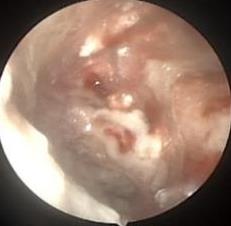

摘要:目的 探讨耳内镜下耳屏软骨-软骨膜鼓膜修补术后的短期疗效。方法 回顾性分析2019年9月-2022年8月该院收治的78例鼓膜穿孔患者的临床资料,患者均采用耳内镜下鼓膜修补术。术后随访3个月,观察鼓膜形态和穿孔愈合情况,记录内镜图像、干耳时间、术前术后听力及耳鸣情况,以及外耳道狭窄等并发症的发生率。结果 术后3个月,鼓膜穿孔愈合率为97.44%(76/78),愈合良好,平均气导听阈较术前明显改善,气骨导间距较术前明显缩小,耳鸣较术前明显改善,差异均有统计学意义(P<0.05)。干耳时间为(4.21±1.12)周。术后出现肉芽5例,再穿孔2例,真菌感染2例,术腔感染、耳屏感染、外耳道狭窄和切口瘢痕各1例,所有患者术后均未发生面神经麻痹和感音神经性聋等严重并发症。结论 耳内镜下耳屏软骨-软骨膜鼓膜修补术是一种安全、有效的手术方法。根据术后愈合规律、内镜下鼓膜和外耳道形态特征,可为鼓膜修补术后正常中耳转归和并发症的诊疗,提供临床参考。